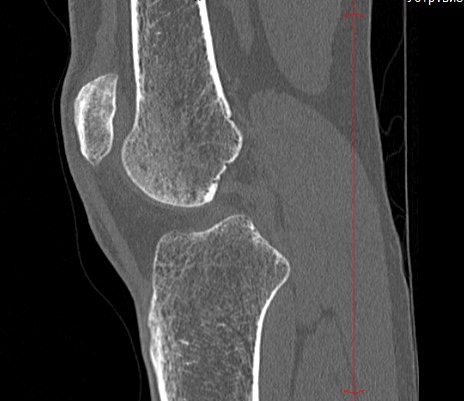

Одним из наиболее информативных методов исследования коленных суставов является мультиспиральная компьютерная томография. КТ относится к лучевым методам исследования и основана на применении ионизирующего излучения с последующей цифровой обработкой данных, полученных при КТ-сканировании.

В наших медицинских центрах обследование коленного сустава проводится на современных мультиспиральных компьютерных томографах последнего поколения TOSHIBA AQUILION. При помощи рентгеновских лучей аппараты послойно сканируют в разных плоскостях исследуемую область с толщиной среза от 0,5 мм. В результате получаются детальные снимки и цифровые трехмерные изображения коленного сустава в мельчайших подробностях. Помимо точности и достоверности диагностики современные компьютерные томографы обеспечивают для пациента минимальную дозу рентгеновского облучения.

Мультиспиральная компьютерная томография дает возможность оценить структуру костной ткани, выявить переломы, воспалительные изменения, участки деструкции костей и диагностировать опухолевые образования. Мультиспиральная КТ часто применяется в ортопедии и травматологии. За счет быстроты, доступности и неинвазивности (то есть обследование выполняется без вмешательства в организм) метод незаменим при травмах сустава, а также при планировании оперативных вмешательств, например, в случае эндопротезирования сустава. В послеоперационном периоде КТ помогает оценить эффективность проведенной операции, вовремя выявить осложнения и отследить процесс восстановления.

Что показывает КТ коленного сустава

- переломы костей;

- артроз;

- артрит;

- скопление жидкости в суставе;

- кисту Бейкера;

- костные наросты на поверхности сустава;

- новообразования

- полные или неполные вывихи — по смещению образующих сустав элементов относительно друг друга;

- деформирующий остеоартроз, ревматический полиартрит

- злокачественную или доброкачественную опухоль

- гемартроз

- абсцесс.